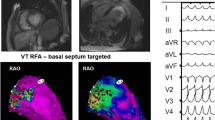

3.4 Dynamic changes in SAECG during long-term follow-up

Before VT ablation, SAECG (t1) was pathological in 27 (82%) out of 33 patients. In the VT recurrence group (13 patients), 12 (92%) patients had abnormal SAECG (t1) while in the non-recurrence group (20 patients), 15 (75%) patients demonstrated abnormal SAECG (t1); P = 0.364. Post-interventionally, SAECG (t2) returned to normal in 8 patients, resulting in significantly less abnormal SAECG after RFCA (t2) compared with SAECG before RFCA (t1): 19 (57.6%) vs. 27 (82%) patients respectively; P = 0.008. Examples of SAECGs after RFCA are shown in Figs. 1 and 2. At the end of the follow-up (t3), SAECG (t3) was available in 21 patients. Of these, the SAECG (t3) remained abnormal in 12 (57%) cases, which is a comparable finding with the SAECG immediately after RFCA (t2) (Fig. 3).

Example of an improvement in SAECG. An example of SAECG before ablation (a) which improved afterwards (b) and the voltage map with the ablation points (c). The corresponding CMR-LGE (cardiovascular magnetic resonance imaging with late gadolinium enhancement (d)) shows an area of microvascular obstruction due to CA